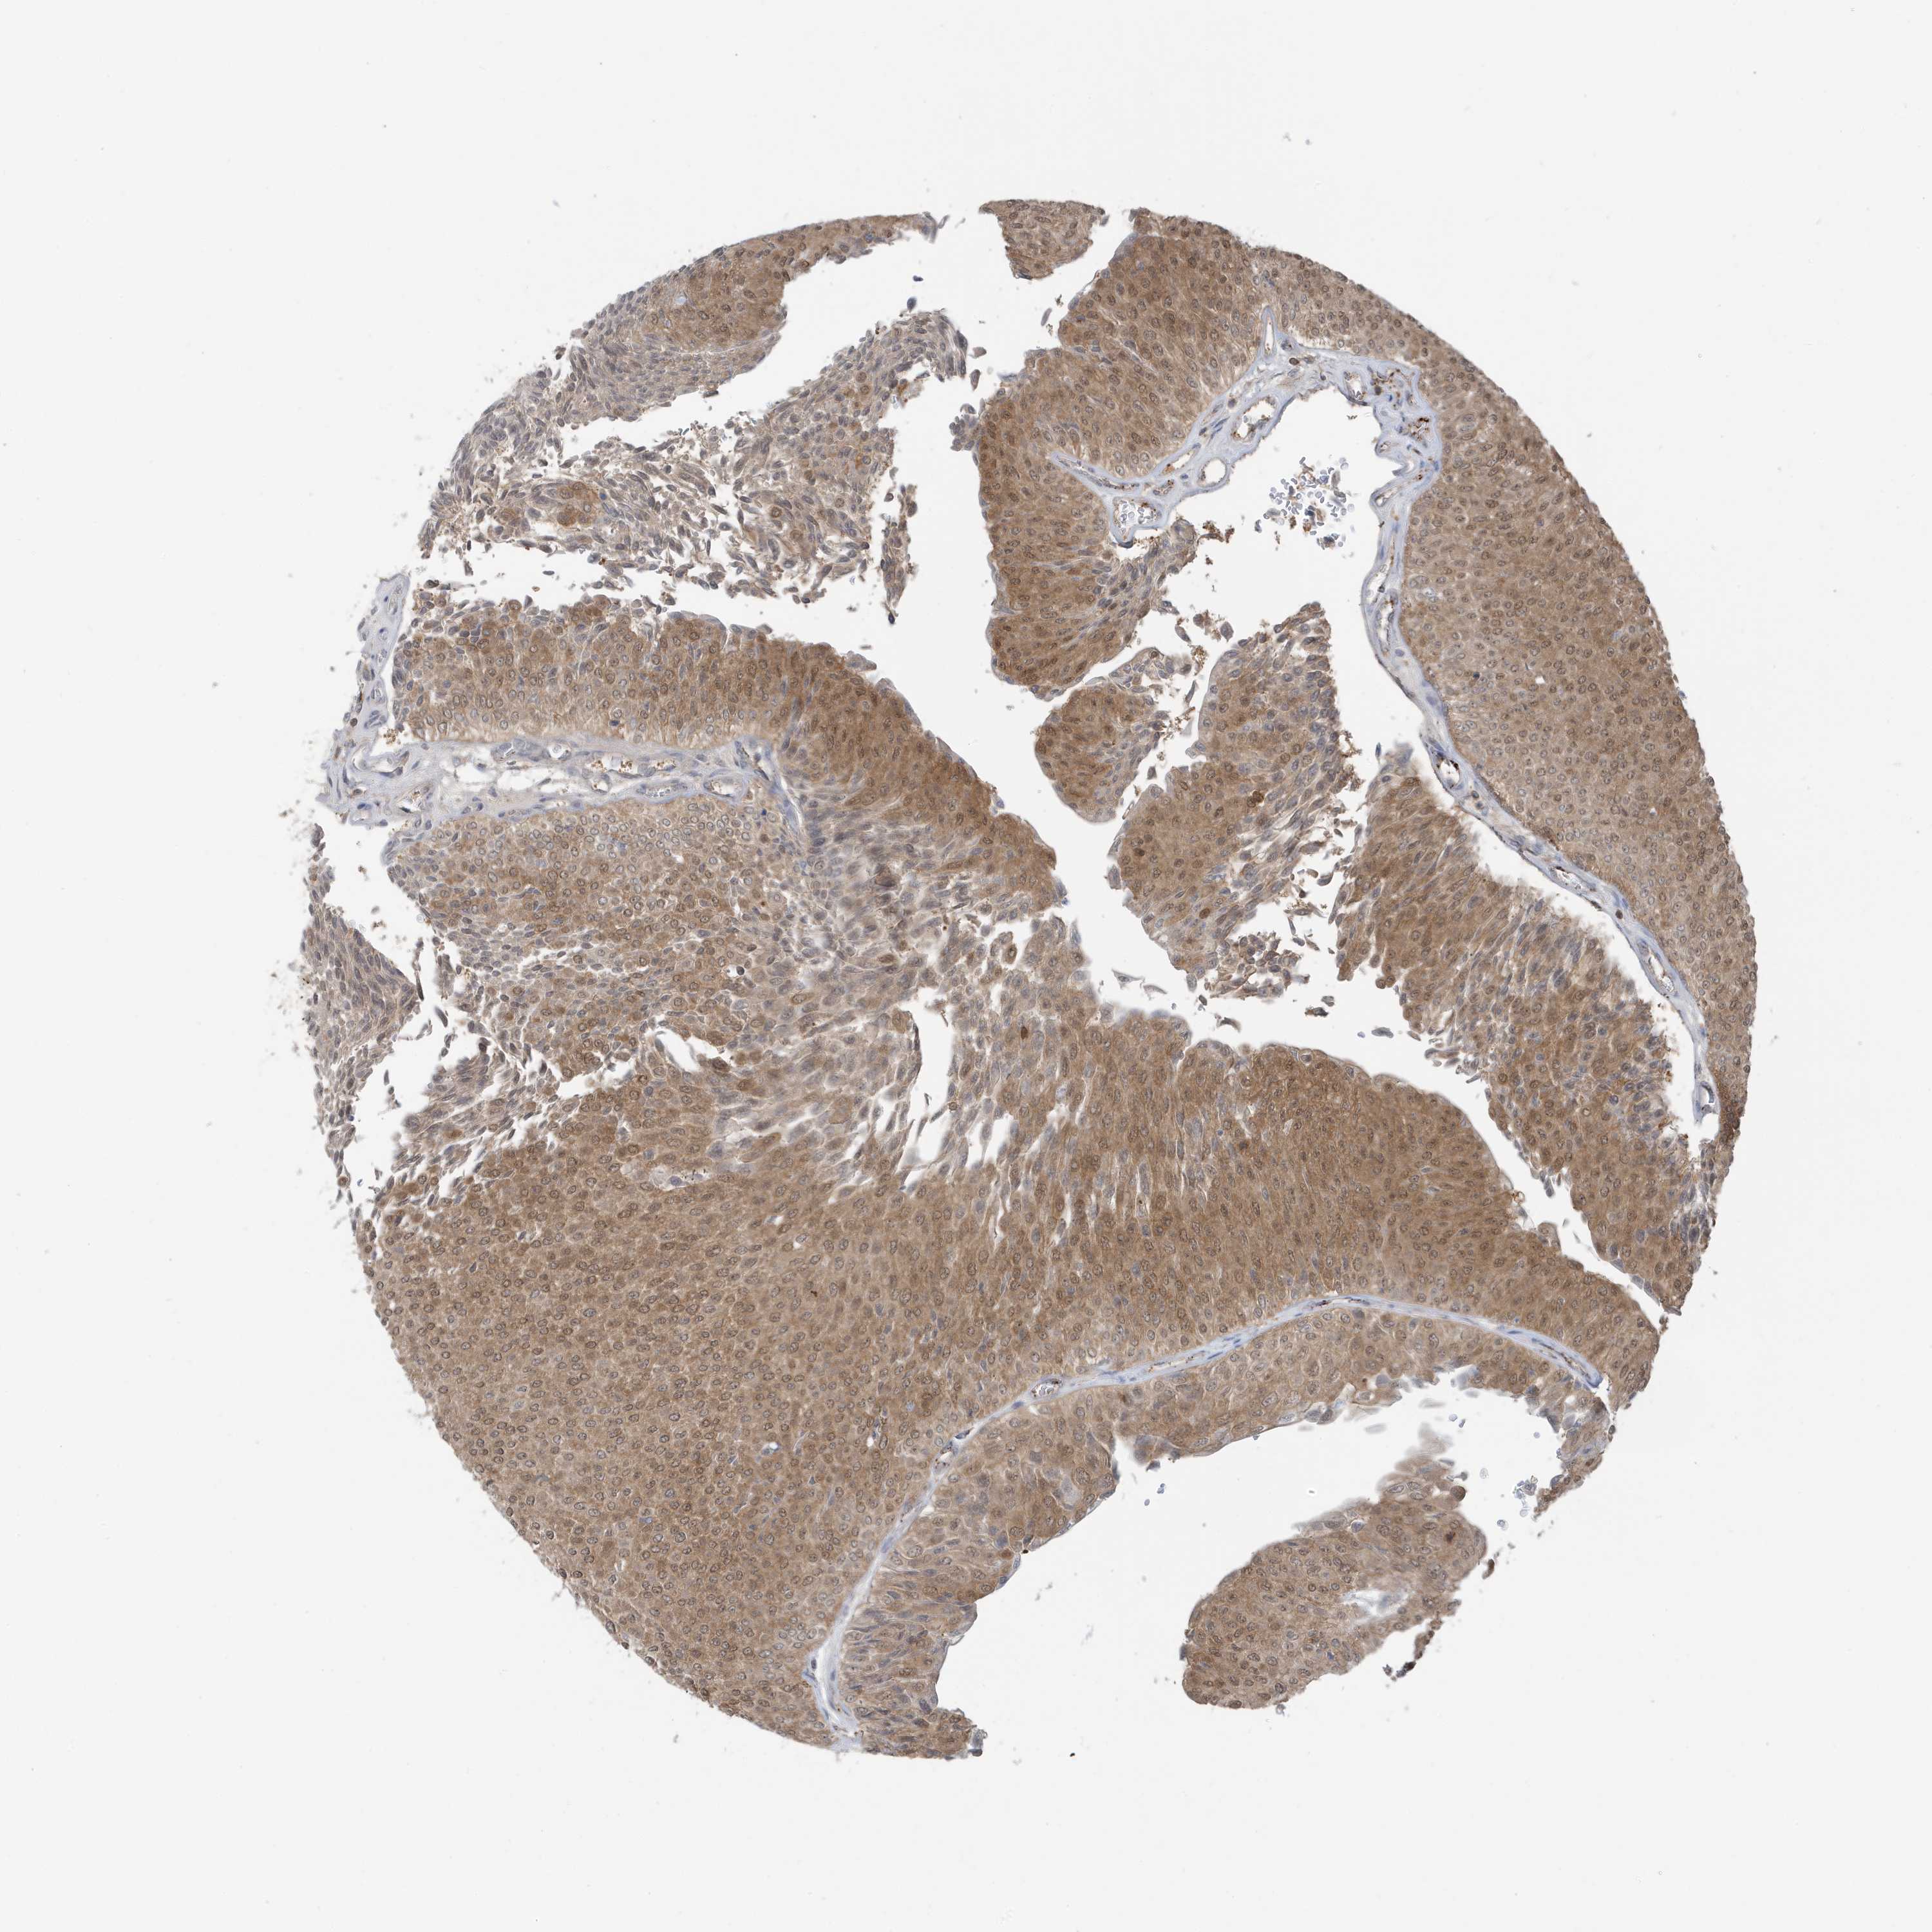

UROTHELIAL CANCER - Protein expressioni

A mouse-over function shows sample information and annotation data. Click on an image to view it in a full screen mode. Samples can be filtered based on level of antibody staining by selecting one or several of the following categories: high, medium, low and not detected. The assay and annotation is described here.

Antibody stainingi

Antibody staining in the annotated cell types in the current human tissue is reported as not detected, low, medium, or high, based on conventional immunohistochemistry profiling in selected tissues. This score is based on the combination of the staining intensity and fraction of stained cells.

Each image is clickable and will lead to virtual microscopy that enables deeper exploration of all samples and also displays staining intensity scores, fraction scores and subcellular localization as well as patient and tissue information for each sample.

Antibody HPA036141

Staining

High

Medium

Low

Not detected

Intensity

Strong

Moderate

Weak

Negative

Quantity

>75%

75%-25%

<25%

None

Location

Nuclear

Cytoplasmic/membranous

Cytoplasmic/membranous,nuclear

Urothelial carcinoma, Low grade

Urothelial carcinoma, High grade